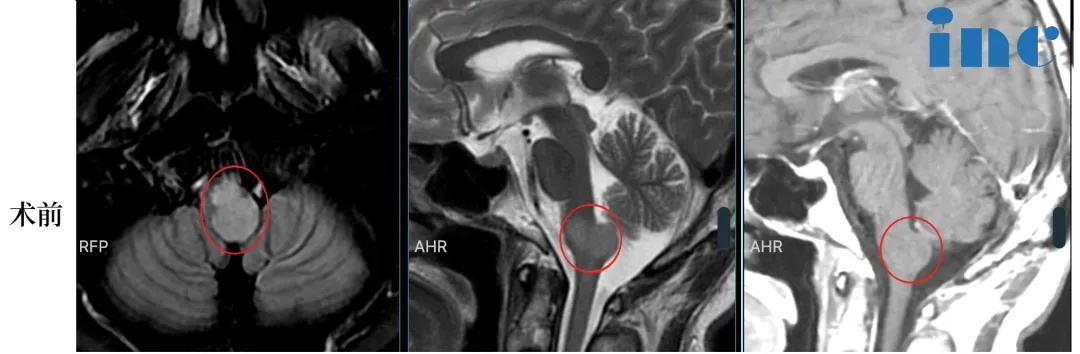

21岁男性-脑干低级别胶质瘤,2个月迅速生长8mm

2021年2月,21岁的张远出现剧烈头痛伴呕吐,并有眼球向上运动困难,于当地医院行颅脑磁共振检查,提示中脑顶盖占位性病变,较大直径约8mm。但是对于这个位置,当地医生也表示无法手术……

2022年8月张远病情再次加重,眼球活动受限,眼球向下运动困难,后脑勺偶然还会感到麻木或疼痛。复查磁共振提示肿瘤增大,此时肿瘤较大直径12mm,一年半内生长4mm。

然而,这个肿瘤不曾停止生长,2022年10月复查核磁提示肿瘤增大,自行测量肿瘤大小约18mm,两月内竟激增6mm!

肿瘤正以惊人的态势恶化,再拖下去,肿瘤会引起吞咽苦难、瘫痪等难以想象的后果,那时候再手术,也无法达到理想的效果。在咨询巴教授得到了“病人不能等太久”“手术目的是完全(全切)或几乎完全(98-99%)切除肿瘤”的答案后,他们争取到了巴教授中国示范手术的机会。

巴教授远程咨询回复:不能等太久

2022年12月3日,张远于苏州大学附属四医院(苏州市独墅湖医院)医院接受巴教授主刀的手术,实现近全切。